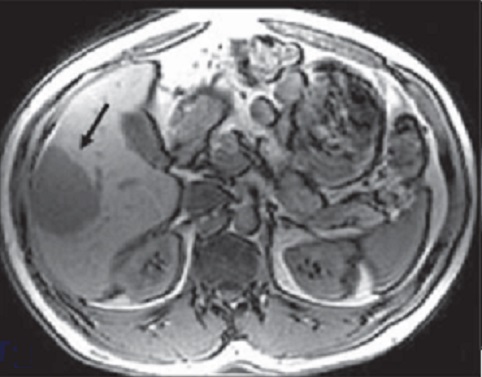

Image

radiologique IRM de kyste du foie : Image lesionel arrondie

ou ovalaire hyposignal en T1 et hypersignal en T2 et nette sủr

T1 + gadolinium FS

Image ỈRM ponderation T1

en coupe axiale d'une kyste simple du foie gauche ,avec

aspect lesionaire ovalaire a hyposignal situe au foie gauche

|

Meme cas

en ponderation T2 : Image lesionnel est tres hypersignal

situe au foie gauche |

Aspect de ce cas ponderee en

T1 + gadolium FS : Image ovalaire a hypodense du foie

gauche |